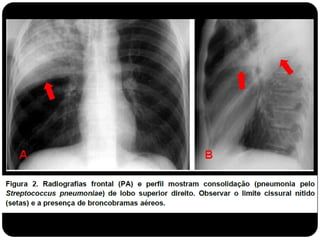

 O padrão alveolar ou do espaço aéreo é caracterizado por

opacidade homogênea.

 Ocorre pela ocupação do espaço aéreo por outras

substâncias que não o ar: exsudato nas pneumopatias,

transudato nos edemas pulmonares, sangue, células

neoplásicas e materiais estranhos no caso de aspiração (ex.

aspiração de óleo mineral)

Padrão alveolar

 Consolidação: substituição do ar alveolar (não há redução de

volume);

 Quando ocorre essa consolidação os brônquios em seu

interior podem tornar-se visíveis – broncograma aéreo.